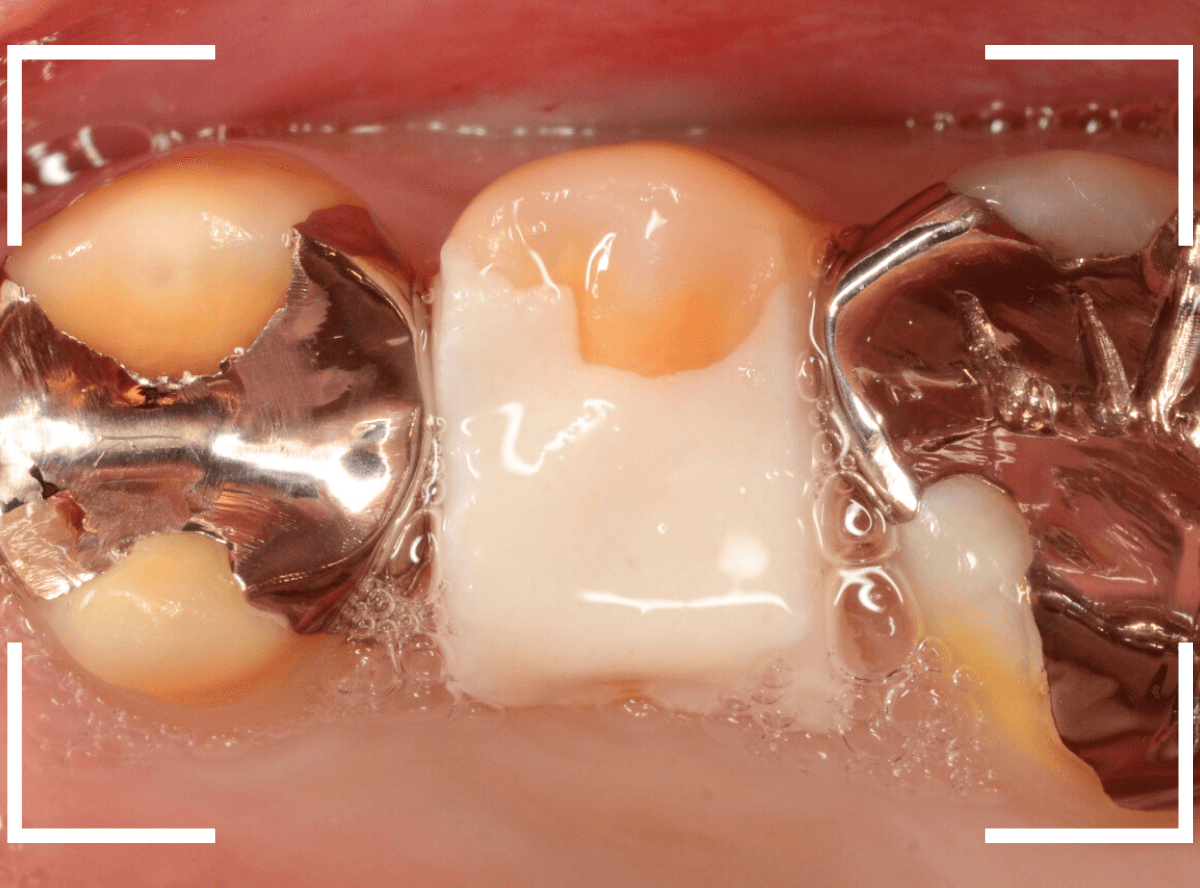

まず、CAD/CAM冠を外します。

中のメタルコアも外して再製します。

歯を傷つけないように、時間をかけてそ~っとメタルコアを除去します。

メタルコアを除去して中を調べてみると、うっすらと虫歯になっていました。

このような状況は、入っているものを外してみないとわかりません。

虫歯を一層除去し、型どりします。

メタルコアよりも、歯に優しいファイバー・コアで再製します。

ファイバーコアをsetした状態で、手前の歯とともにトリミングし、もう一度、型どりをします。